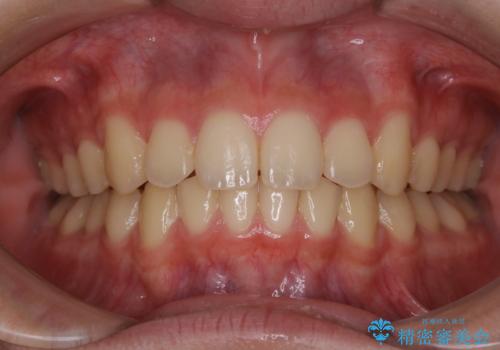

非抜歯で劇的に出っ歯を改善!インビザラインとカリエールの組み合わせ治療

- 患者様、出っ歯のお悩みで来院されました。

骨格の分析を行ったところ上顎も出てはいるのですが、下顎が引っ込んでいる状態であるということがわかりました。

よって上顎の歯を抜いて治療をするのではなく、カリエールという器具を使用して下顎を前に引っ張り出しながら上顎を引っ込めるという治療を行うことにしました。